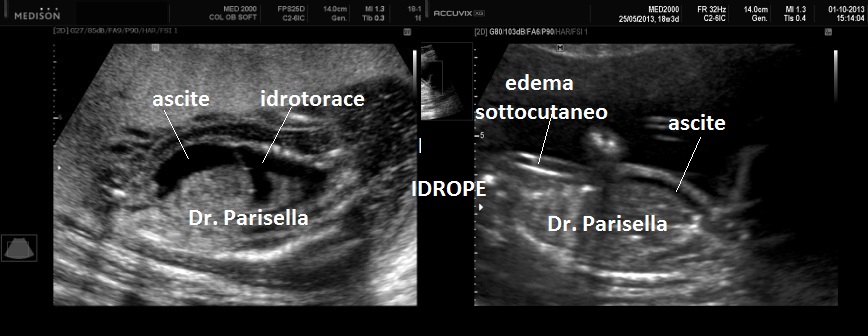

4) idrope .